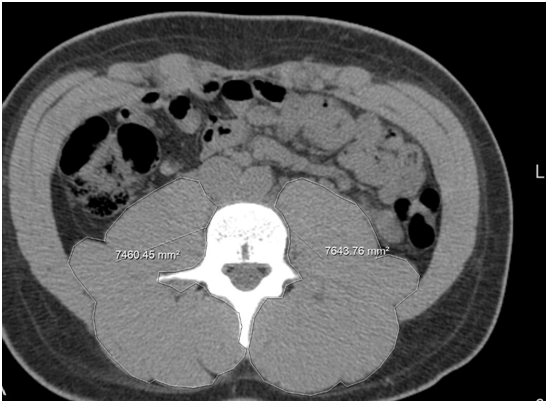

83 patients with NAFLD and 83 C were identified (Table 1). The composition of the groups was similar in terms of age, gender, and body mass index (BMI); the mean age of the patients in the NAFLD group was 48±12years, with 39 subjects (46.9%) being men versus the control group, in which the mean age of the subjects was 46±14years, and 42(50%) were men. The mean BMI was 30.3±5.6kg/m2 in the NAFLD group vs 30.6±6.6 in the control. Patients with NAFLD had a lower psoas and lumbar paraspinal muscle mass than those of patients in the control group (p<0.001) (Table 1). CT images of a patient with NAFLD and a control subject highlighting of lumbar paraspinal muscle areas are shown in Figures 1 and 2, respectively.

Figure 1 Image of a CT scan of a patient with non alcoholic fatty liver disease and sarcopenia, as suggested by decreased psoas muscle area (circle).

Figure 2 Image of a CT scan of a patient from the control group, i.e. without NAFLD. The circle indicates the psoas muscles.